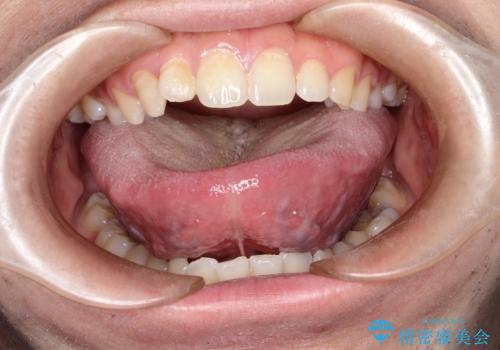

[舌小帯の形成術] 舌の動きが悪い 滑舌を改善したい!

![[舌小帯の形成術] 舌の動きが悪い 滑舌を改善したい!の症例 治療前](https://seimitsushinbi.jp/wp/wp-content/uploads/2025/06/bc8fa7739e67eae233f395e6e973327d-500x350.jpg?v=1750240523)